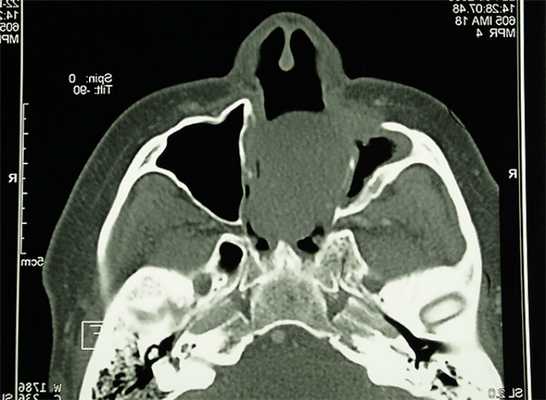

Больная М., 62 лет, обратилась с жалобами на наличие верхнечелюстного дефекта (отсутствие левой верхнечелюстной кости), невозможность пережевывание пищи и попадание ее в полость носа, невнятность, гнусавость речи. Из анамнеза: 4 года назад проведен курс лучевой терапии и выполнена резекция по поводу C-r левой верхней челюсти T3N0M0. Объективно: нарушение конфигурации лица за счет левосторонней рубцовой деформации и западения мягких тканей верхней губы, щечной и подглазничной областей. Открывание рта в полном объеме, не затруднено. Определяется отсутствие левой верхнечелюстной кости. Костный изъян эпителизирован рубцово-измененной слизистой оболочкой. Зубная формула: 15, 12, 11, 37, 35, 34, 33, 32, 31, 41, 42, 43, 44, 48. Дефекты нижнего зубного ряда восстановлены штампованно-паянным мостовидным протезом справа и металлокерамическим мостовидным протезом слева. В проекции верхнечелюстного бугра справа установлен дентальный имплантат (рис. 3) . Рентгенологическая картина представлена на рис. 4 . Фонетическое обследование больной с помощью разработанного способа диагностики нарушений речевой функции, включающего оценку произношения звуков и разборчивости речи (гнусавости) с помощью карты-опросника, с последующим математическим вычислением процента дефектности речи (пат. РФ № 2284744) [30] показало, что нарушено произношение звуков: б, в, г, д, ж, з, к, л, м, н, п, р, с, т; коэффициент разборчивости речи — 5; величина нарушения речевой функции — 50,5 %. DS: субтотальный пострезекционный верхнечелюстной дефект (отсутствие левой верхнечелюстной кости), частичная верхнечелюстная адентия I класса по Кеннеди.

Рис. 3а. Состояние полости рта больной М. до ортопедического лечения: положение закрытого рта (фронтальная проекция). Рис. 3б. Состояние полости рта больной М. до ортопедического лечения: положение открытого рта (полуаксиальная проекция).

Рис. 4а. Больная М., объемное компьютерное рентгеновское изображение черепа: фронтальная проекция. Рис. 4б. Больная М., объемное компьютерное рентгеновское изображение черепа: левая латеральная проекция.